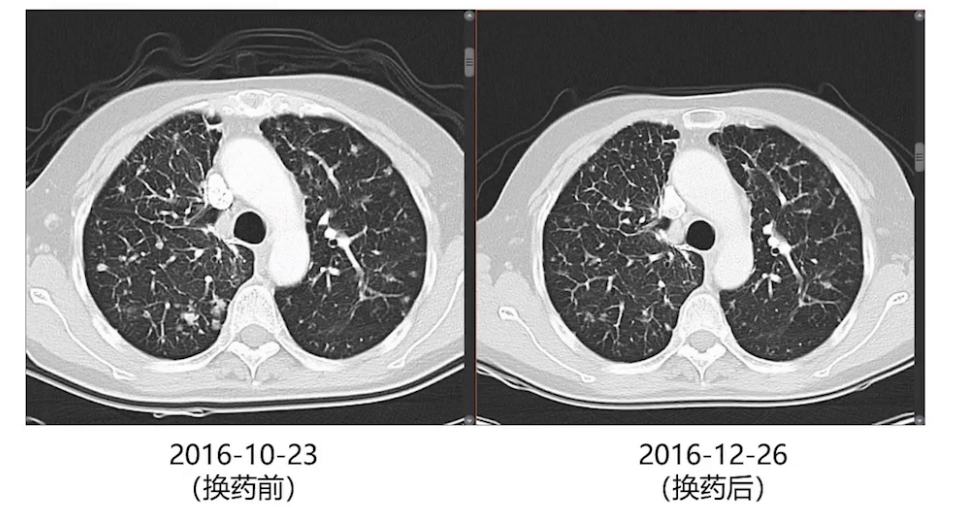

术后3个月、6个月及9个月复查,双肺结节逐渐增大,考虑厄洛替尼耐药,2016年10月改服奥西替尼。两个月后影像复查,双肺增大的结节再次缓解。此后每2-3个月复查胸部增强CT,每半年进行一次全身检查。